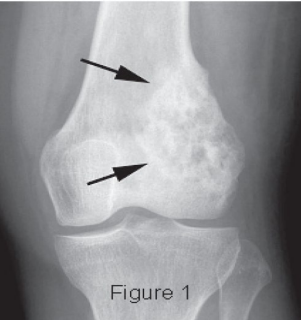

bone, 10-18, mesenchymal, metaphyses, long, femur, tibia, pain, redness, lung, fracture

Osteosarcoma: Background

-Most common malignant _____ tumor in childhood

-Epidemiology → ___-___ years old

-Pathogenesis → Arises from bone producing ___________ cells

Occurs mainly in the __________ of ____ bones

Distal end of _____ or proximal end of _____ (MC)

Can extend beyond the bone into the soft tissues

-Symptoms → _____, swelling/warmth/_________ over the area, cough/SOB/chest pain if _____ mets, limp, pathologic __________

MRI, primary, CT, biopsy, osteoid, resection

Osteosarcoma: Diagnosis and Treatment

-Diagnosis

___ to evaluate extent of the _________ tumor

Metastatic evaluation with bone scan and chest __

Tissue _______ (confirms), shows presence of _______

-Treatment

Chemotherapy

Surgical ___________